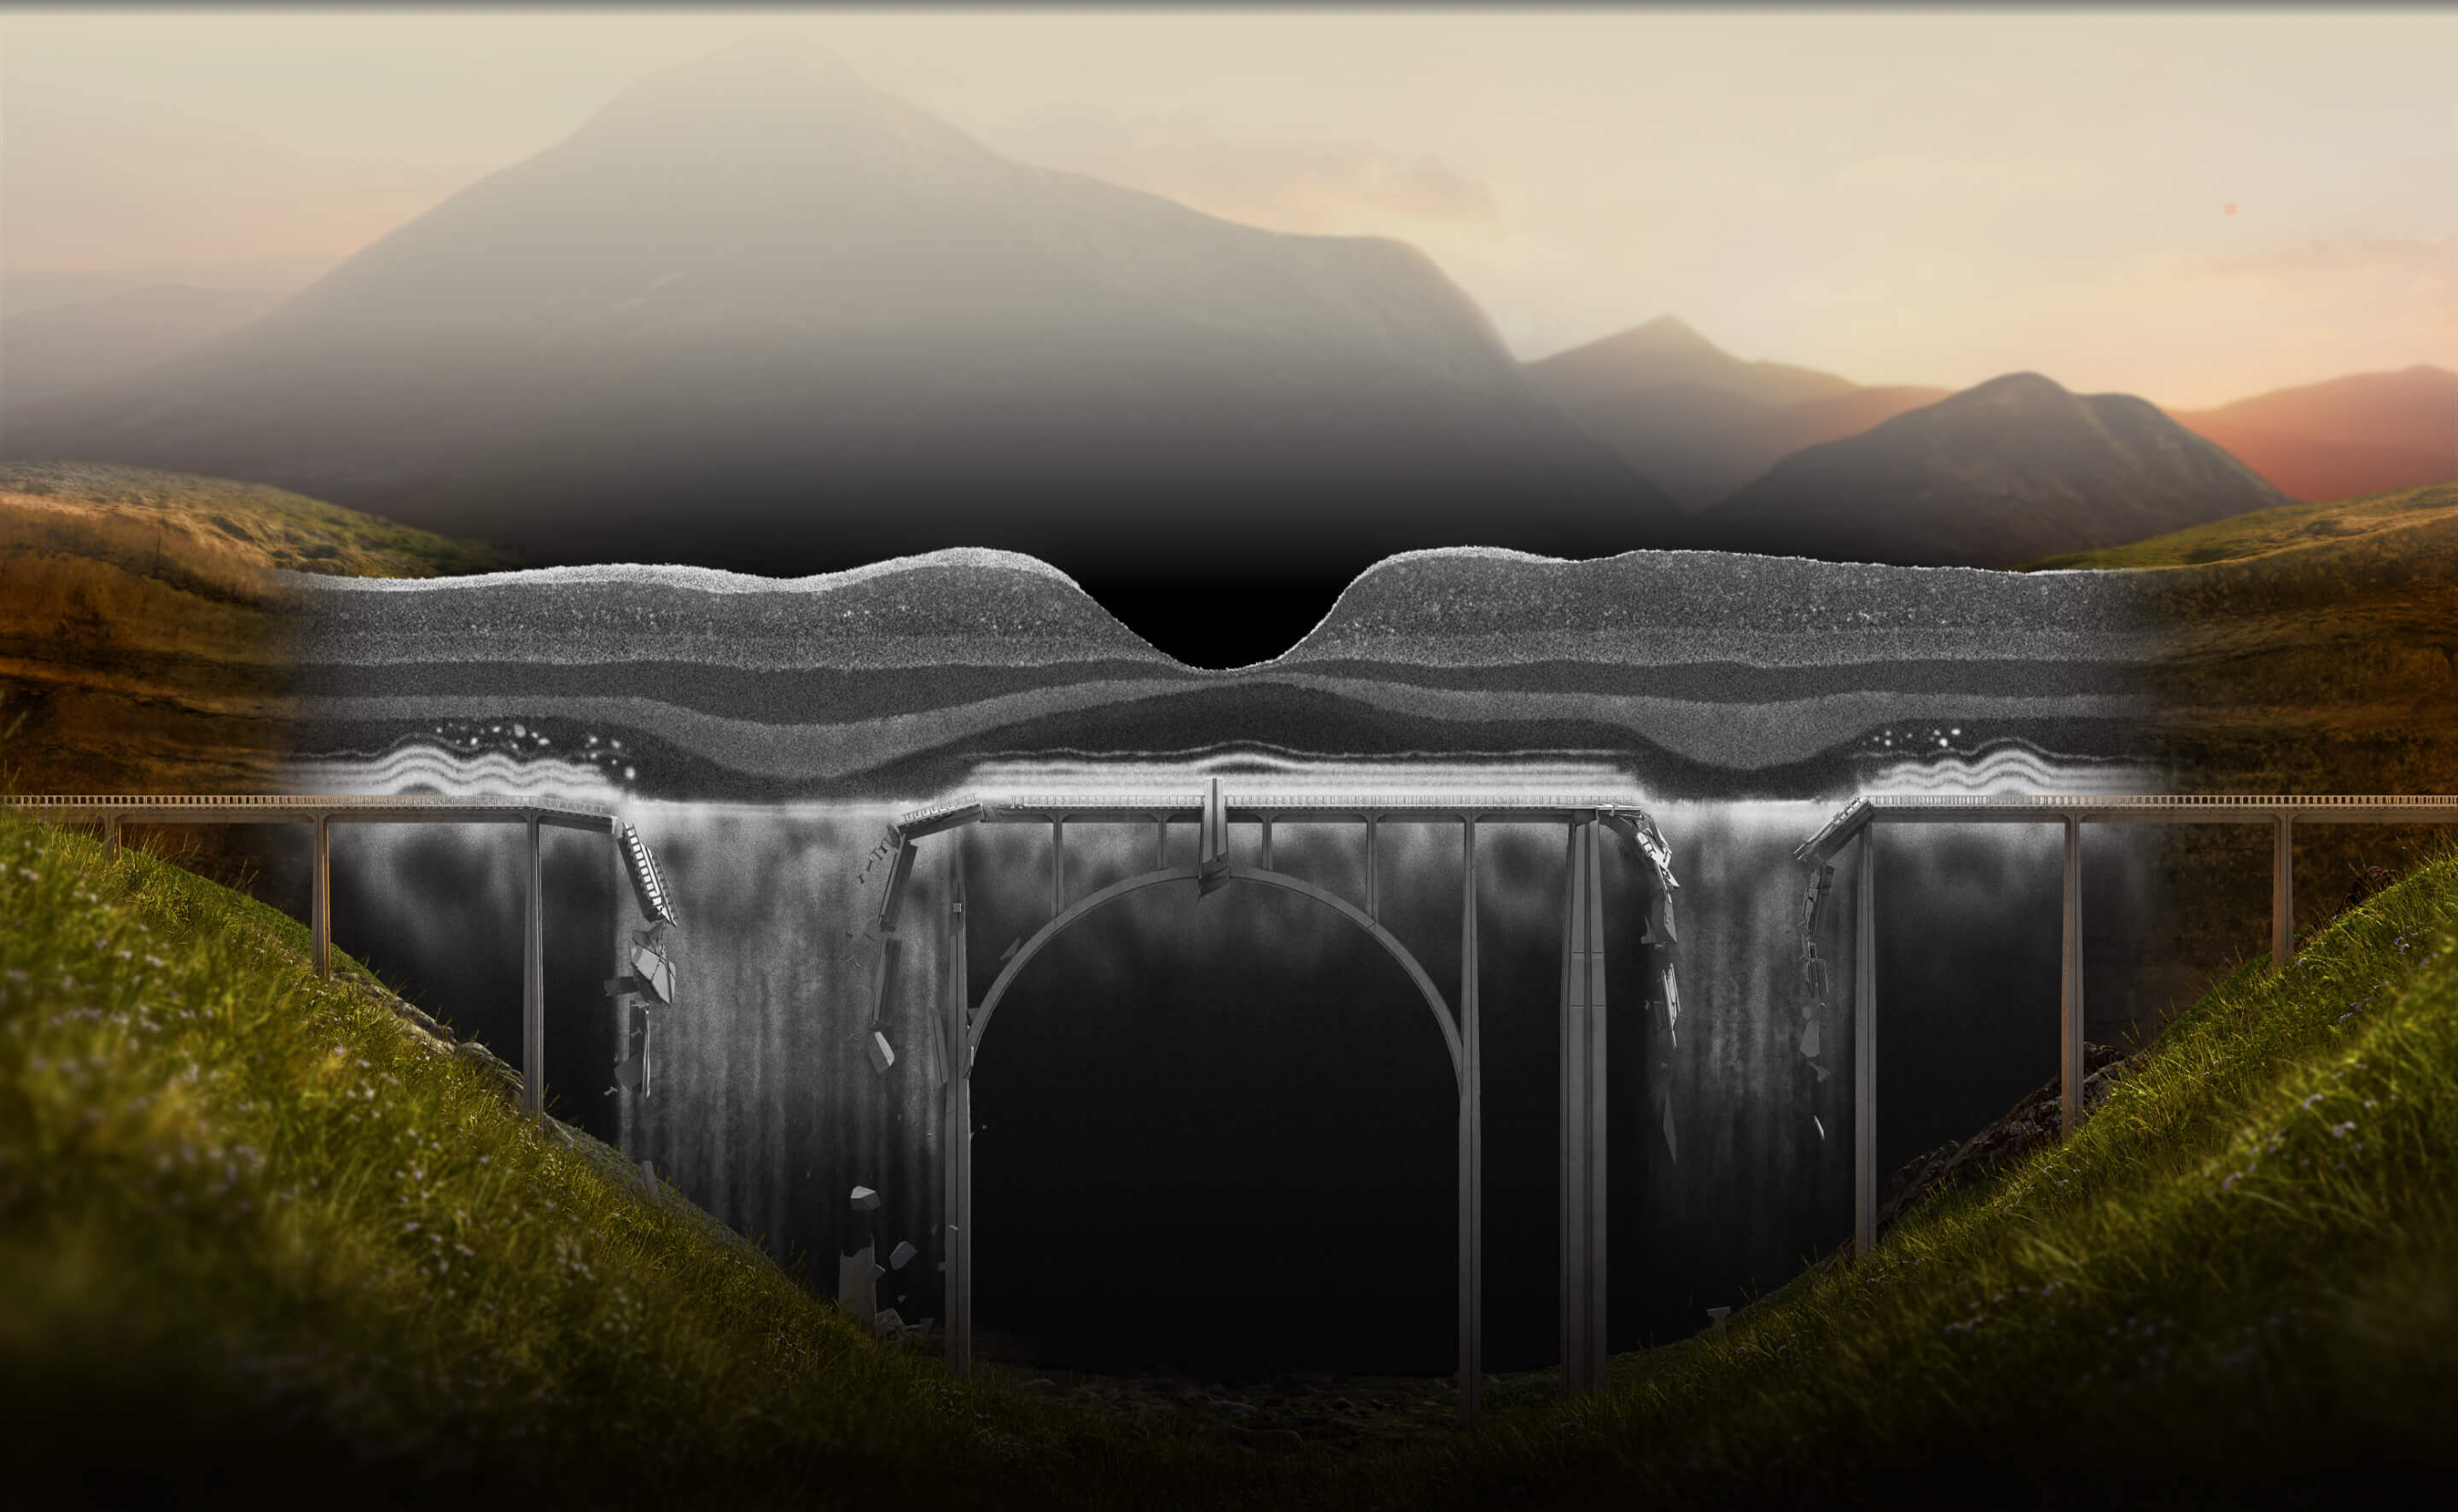

SEE THE SIGNS OF GEOGRAPHIC ATROPHY (GA)

GA can destroy so much

It is critical to recognize GA and refer patients in a timely manner, as disease progression is relentless and irreversible1,4-8

Learn how to recognize GA